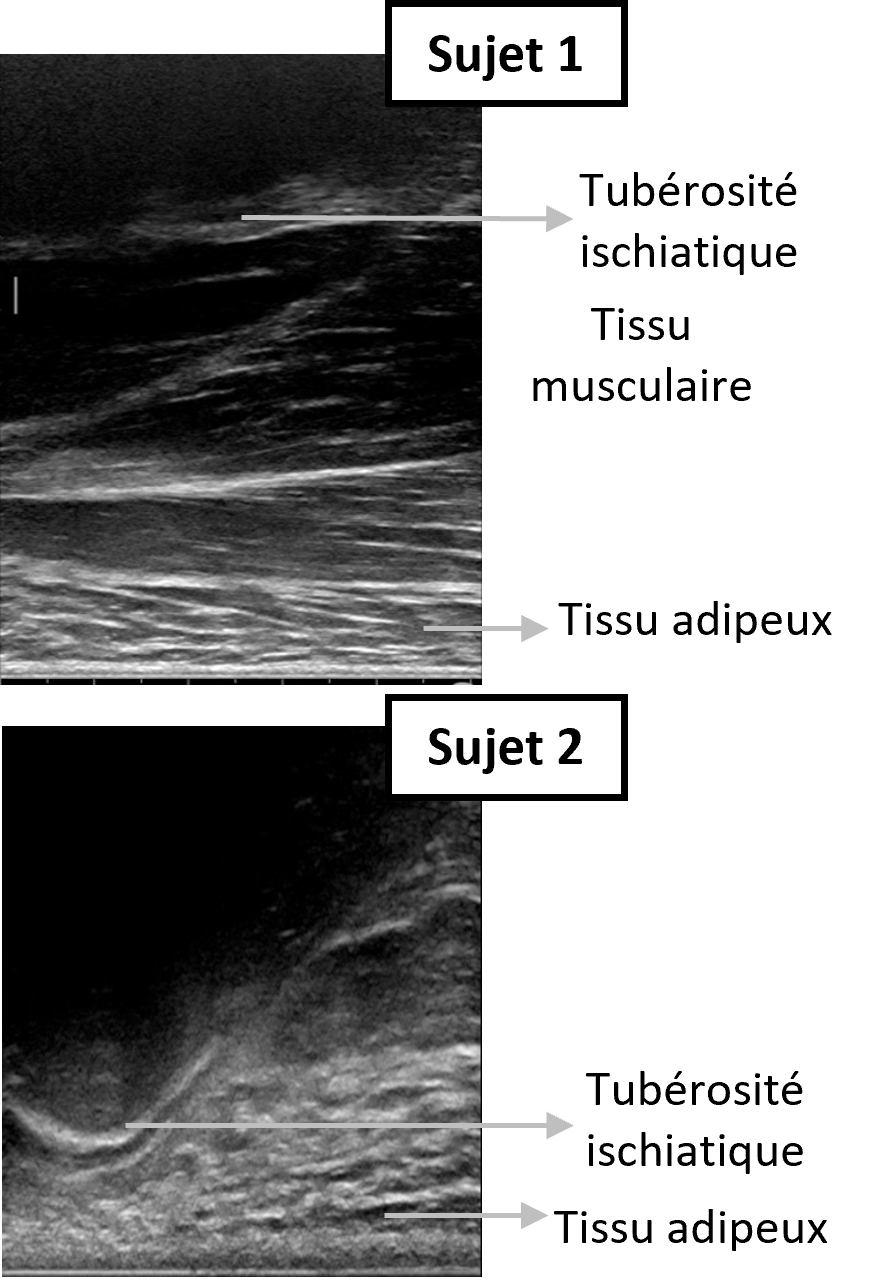

Les résultats confirment des observations antérieures sur la perfusion tissulaire sous charge : le flux sanguin cutané chute brutalement dès le début de l’assise, puis se stabilise autour de 400 secondes et reste faible tout au long de l’expérience [5]. Pour des pressions moyennes de 8 à 12 kPa (9,8 ± 0,7 kPa pour les sujets âgés, 9,3 ± 1,3 kPa pour les jeunes) et des pics atteignant 57 kPa, le flux sanguin diminue en moyenne de 75 % par rapport au repos et ne revient pas aux valeurs hors chargement après 3, 5 ou 11 minutes de décharge. De plus, les sujets âgés présentent une déformation du tissu adipeux bien plus marquée avec un ratio d’épaisseur finale/initiale de 0,30 ± 0,06 contre 0,74 ± 0,19 chez les jeunes (p = 0,0003), tendance à confirmer sur un plus grand échantillon. L’échographie révèle deux morphologies distinctes sous la tubérosité ischiatique en position assise : seul un sujet jeune présente trois couches différenciées (graisse, muscle, os), tandis que les 8 autres ne présentent pas de tissu musculaire sous la tubérosité ischiatique en position assise (Figure 2). Ce constat, cohérent avec Sonenblum et al. [8], souligne l’importance du rôle du tissu adipeux, premier tissu indenté par l’ischion, dans le risque d’escarre. Enfin, aucune corrélation n’a été trouvée entre la pression d’interface, la baisse de flux sanguin cutané et l’épaisseur du tissu adipeux, suggérant que la mesure de la pression seule ne suffit pas à prédire le risque d’ischémie, et a fortiori le risque d’escarre.

Figure 2. Différentes morphologies observable sous la tubérosité ischiatique par échographie en position assise. Sujet 1 présentant différents chefs musculaires entre la tubérosité ischiatique et le tissu adipeux, sujet 2 absence de tissu musculaire dans cette configuration.